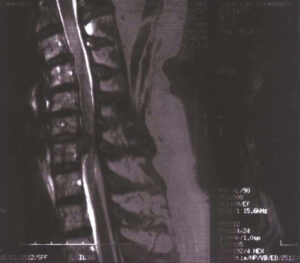

La risonanza magnetica mostra l’effetto ottenuto dopo un mese di trattamenti, per un totale di dodici sessioni, utilizzando protocolli di lavoro con piastre capacitive automatiche ed elettrodo resistivo, alla frequenza di 1MHz.

Risonanza magnetica prima del trattamento

Risonanza magnetica dopo il trattamento